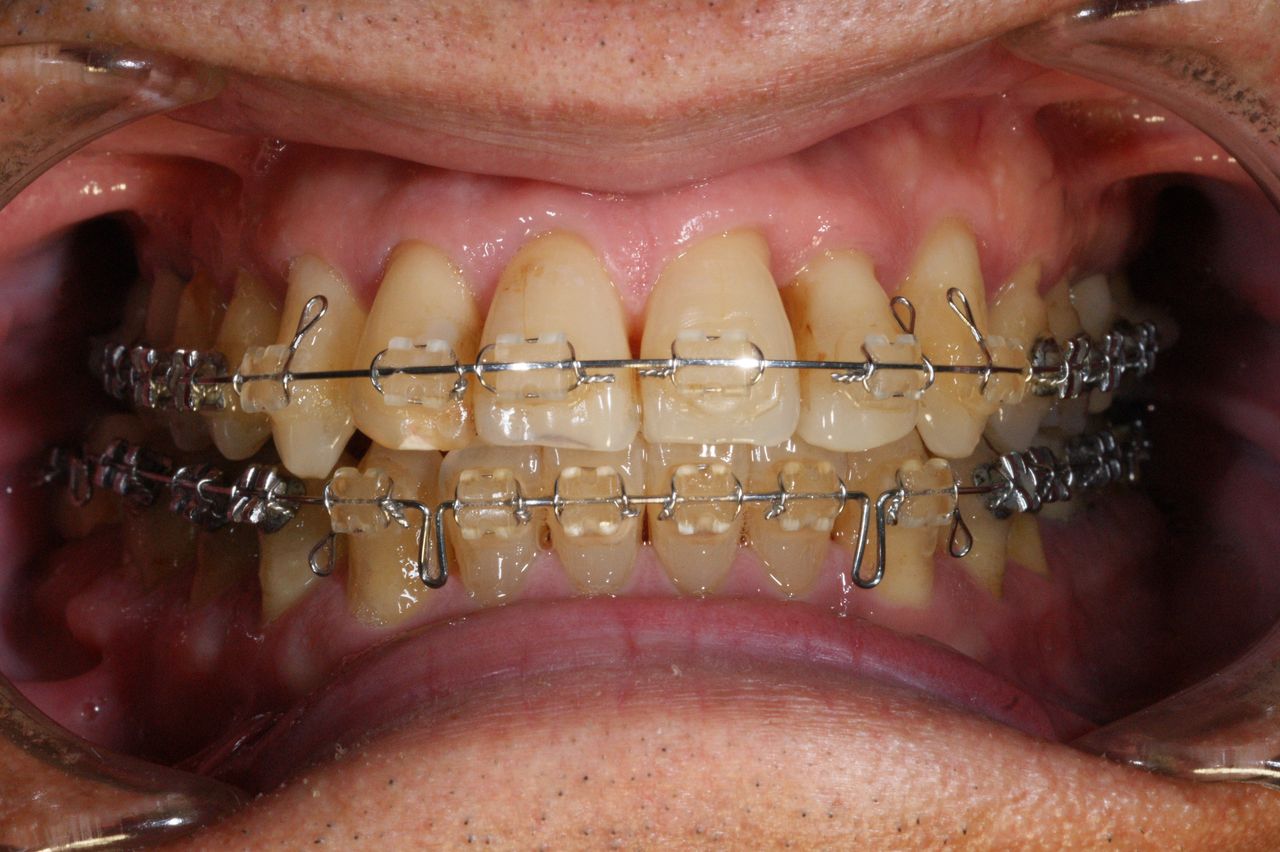

通法にしたがい、主訴に対する処置および必要なう蝕処置、根管治療等を行いながらブラッシング、歯石除去、根面滑沢化の歯周病初期治療を進めていった。

再評価の結果、一部の歯周ポケットに改善がみられるも歯周病を根絶するためには外科処置を回避することは不可能と判断し、そのむねを患者さんに説明、同意が得られたので必要な部位に歯周外科を行う。

3か月後再評価し、炎症性物質が廓清されたものと判断したので、歯科矯正施術へのステージへと移行する。